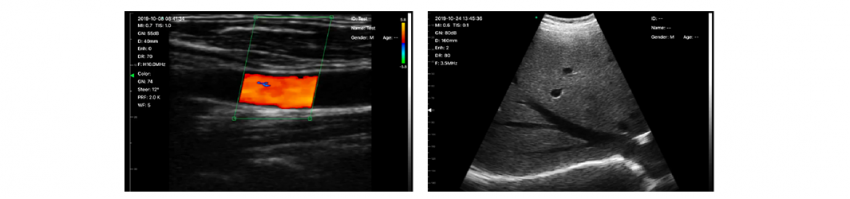

And the last manufacturer we would like to consider is a Chinese manufacturer of WI-FI transducers Sonostar. Like Konted, the probe has 2 lenses - convex and linear.

A powerful PR campaign Sonostar has never held, the most minimalistic website, which on one page sets out all the necessary information for the potential user and added clinical images.

The transducer weight: 230 grams; frequency is 7.5-10 (linear) and 3.5-5 (convex).

The functionality of the device includes B, B+M, M, Color, PW, PDI modes (and they work in all regions, unlike Butterfly). And one of the features is the ability to connect to 3 operating systems (IOS, Windows, Android).

From the clinical packages there is only obstetric and the ability to measure the distance, area and volume of the structures. Sonostar clinical images: